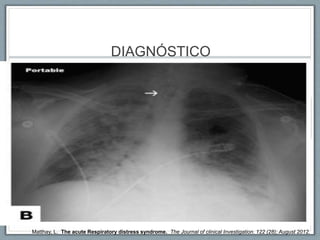

DIAGNÓSTICO

Matthay, L. The acute Respiratory distress syndrome. The Journal of clinical Investigation. 122 (28); August 2012.

DIAGNÓSTICO Infiltrados Pulmonares Bilaterales Hipoxemia Severa PaO2/FiO2<200 Ausencia de Falla ♥ Matthay,L. The acute Respiratory distress syndrome. The Journal of clinical Investigation. 122 (28); August 2012.